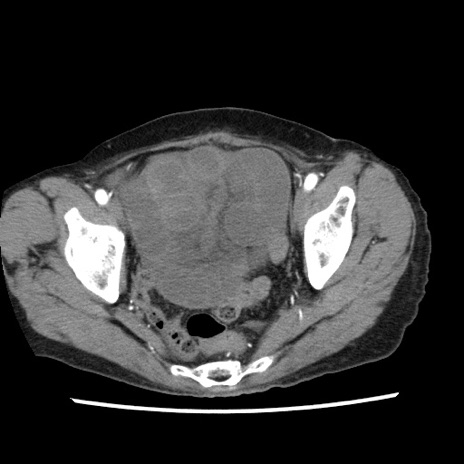

冠状断像